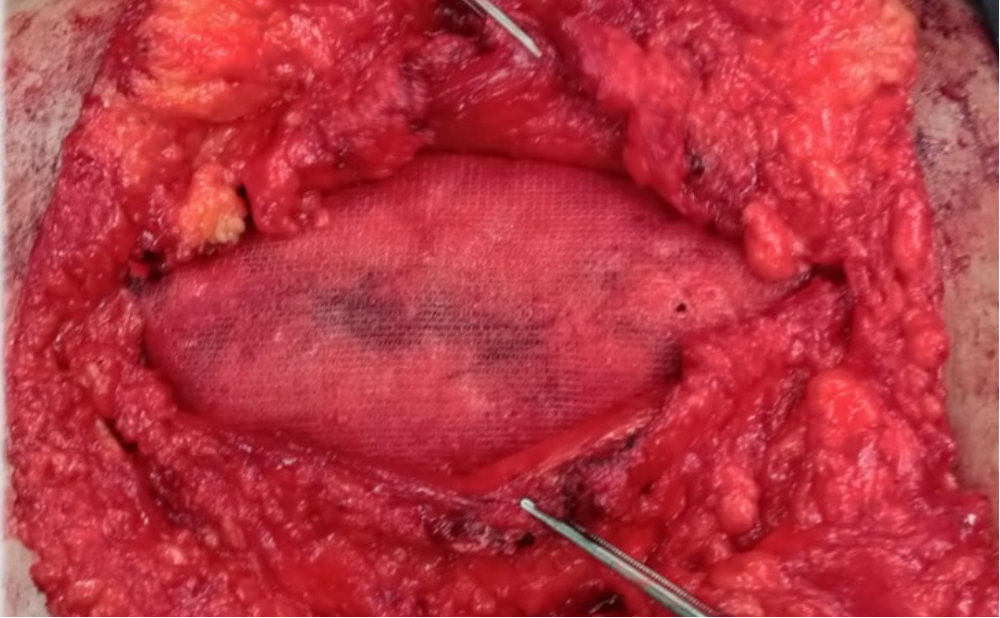

After excision of the old scar tissue, the hernia sac was carefully dissected free and opened, and the abdominal cavity was examined. During the lateral suprafascial dissection, perforating vessels were identified, meticulously isolated, and preserved to maintain blood supply. A longitudinal incision was made in the posterior rectus sheath approximately 5 mm from the midline on each side to enter the retrorectus (Rives–Stoppa) plane. This incision was extended cranially and caudally along the length of the defect, allowing the creation of a wide retromuscular pocket (Figure 1). Blunt dissection was then used to further develop the plane laterally toward the linea semilunaris. An assistant retracted the rectus abdominis (RA) muscle to improve exposure during this dissection. Small perforating vessels between the RA muscle and the posterior sheath were divided as needed until reaching the lateral border of the rectus (the linea semilunaris marked by the neurovascular bundles). These steps achieve the myofascial release of the posterior elements, constituting the PCS.In cases requiring TAR (Group 2 patients with hernias ≥10 cm), the dissection was continued with release of the transversus abdominis(TA) muscle. The lateral neurovascular bundles at the linea semilunaris were first identified to avoid injury. An incision was made in the posterior lamella of the internal oblique aponeurosis, approximately 5 mm medial to the neurovascular bundles, to expose the underlying TA muscle. The TA muscle was then incised along its length to enter the proper pre-transversalis plane (TAR plane). This muscle release was performed using short, controlled bursts of monopolar cautery to divide the muscle fibers bloodlessly. Following completion of the PCS (and TAR, in Group 2), the posterior rectus sheaths were brought together and closed in the midline. A large self-gripping mesh was then placed in the retromuscular space (sublay position) beneath the rectus muscles to reinforce the repair (Figure 2). Closed-suction drains were placed in the retromuscular space on each side. Finally, the anterior rectus sheath (linea alba) was reapproximated and closed using a small-bite technique to minimize tension and reduce wound complications. Operative time, intraoperative blood loss, and postoperative drain duration were recorded for all patients. Postoperative pain was assessed using the Visual Analog Scale (VAS). The presence of seroma and any wound complications (such as infection or dehiscence) was evaluated on postoperative days 1, 7, and 15. Patients were followed at regular intervals (approximately at 1, 3, 6, and 12 months postoperatively) to monitor for late complications and hernia recurrence. Outcome data, including operative time, VAS pain scores, duration of drainage, incidence of seroma, wound complications, and hernia recurrences, were compiled and analyzed. Descriptive statistics (mean, standard deviation, median, and frequency percentages) were used to summarize the data. Statistical comparisons between Group 1 and Group 2 were conducted where appropriate, with a significance level of p < 0.05.

Figure 1. Retromuscular dissection

Figure 2. Reconstruction of the posterior rectus sheaths with self-gripping mesh